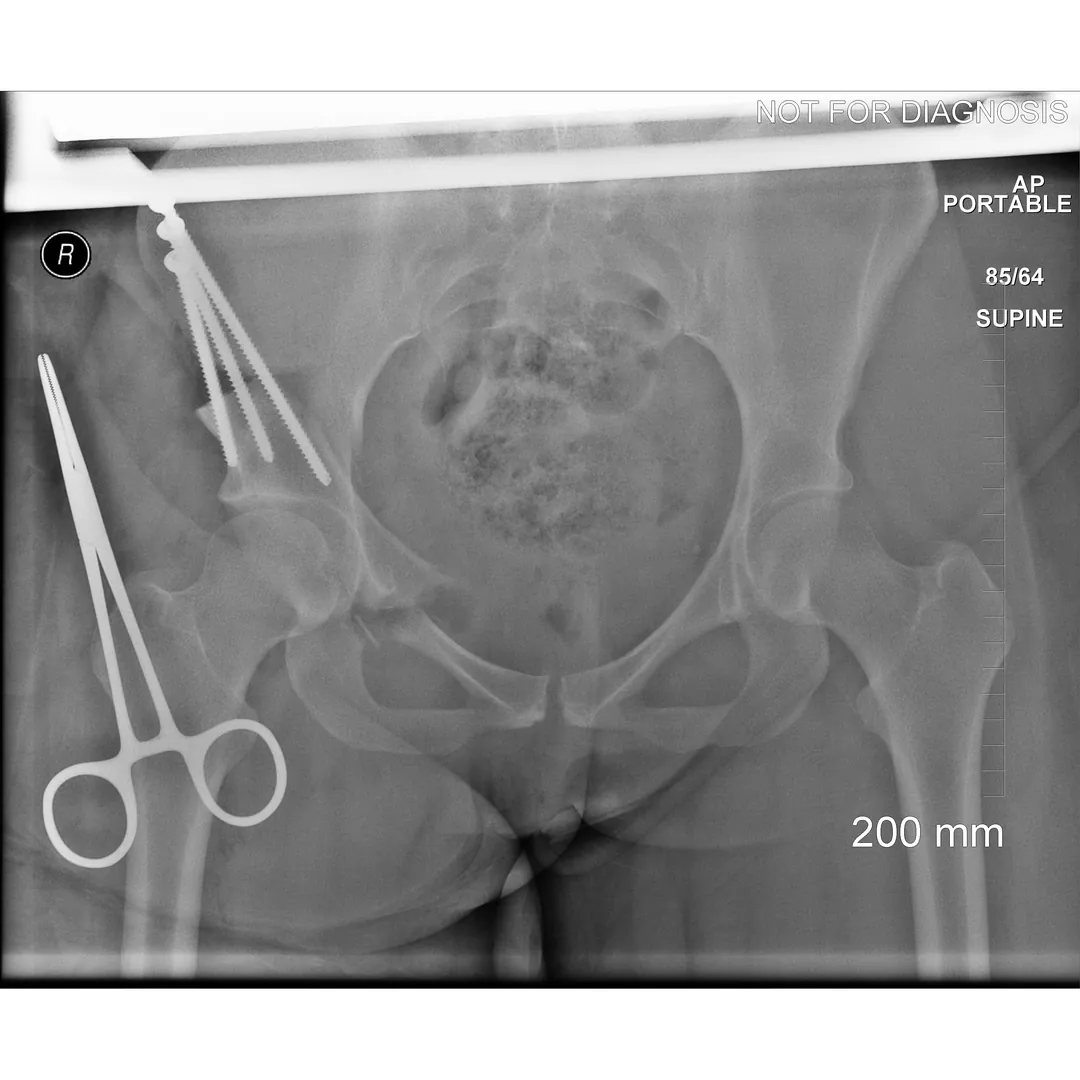

During a PAO, the surgeon carefully cuts the bone around the hip socket and repositions it to provide better coverage of the femoral head. The socket is then fixed in its new position using screws. The goal is to improve hip stability, reduce pain, and preserve the patient’s natural hip joint.

• Screws shown securing the acetabulum in its new position

• Several controlled bone cuts are made around the hip socket

• The socket is repositioned and fixed with screws

• The hip joint itself is preserved